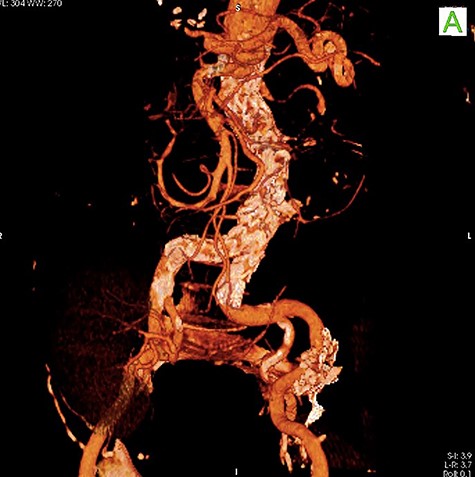

To minimize the risk of injury to renal allograft and avoid facing a hostile-abdomen, the patient was proposed to EVAR. Prior to intervention, upon contrast injection, the aneurysm and the corresponding clot containing the leakage were visualized (Video 1). A bifurcated endograft (Cook Zenith LP) was used and the main body was introduced through the left common femoral artery to reduce the duration of ischemia. The contralateral gate was cannulated and Lunderquist wire was advanced. The right-sided sheath was withdrawn up to the common femoral artery and the ipsilateral limb was deployed (Video 2). The post-operation course was uncomplicated with normal levels of serum creatinine. The patient was discharged 2 days later. One month later, a follow-up CT angiography was performed that demonstrated successful endovascular stent graft placement (Fig. 3).